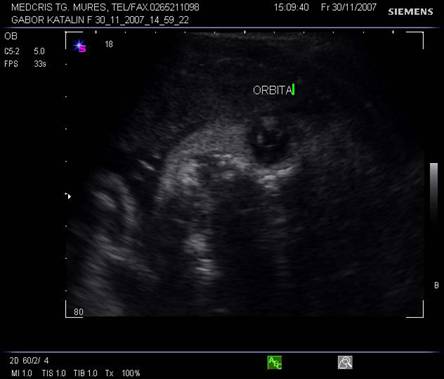

Planul XIII - indica simultan orbitele si regiunea mandibulara, cristalinul apare ca un inel ecogenic in partea anterioara a orbitelor. Miscarile lente sau rapide ale ochilor pot fi cateodata evidentiate.

Planul XIV - plan oblic pentru orbite si nas.